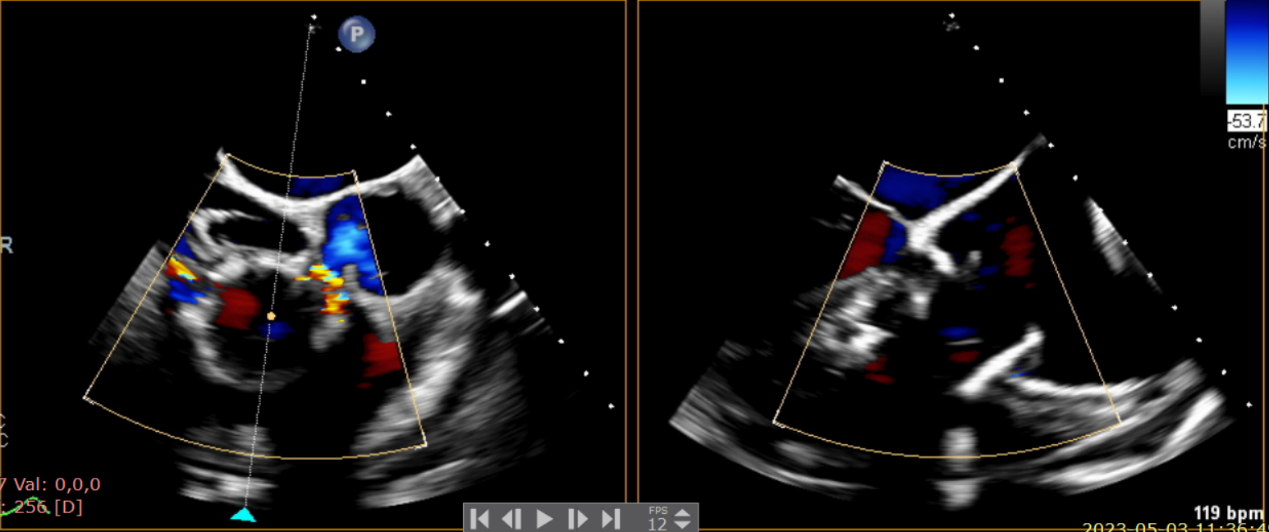

術后超聲提示無瓣周漏

術后超聲提示僅殘余輕微瓣周漏